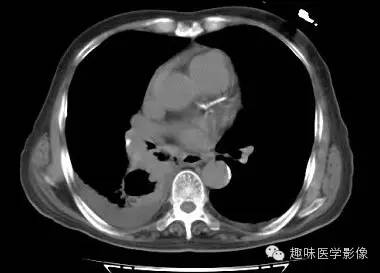

【病例】肺脓肿1例CT影像特点

男,71岁,发热待查。

双肺多发无壁低密度区,以右肺下叶底部为主。右肺下叶见大片不规则实变阴影伴多发空洞影,实变肺组织内见支气管气象,右肺下叶支气管局部显示不清。纵隔内见淋巴结。右侧胸腔内见积液影,邻近胸膜肥厚。主动脉、冠状动脉钙化。

右肺下叶肺脓肿、肺炎伴胸腔积液,肺气肿、肺大泡。

右胸廓变小,心影右移;右肺下叶多房性空洞,空洞内未见明显液平面,右下肺病变应该是下叶阻塞性肺炎,实变肺组织内见支气管气像,邻近胸膜增厚,并合并胸腔积液,支持肺脓肿。